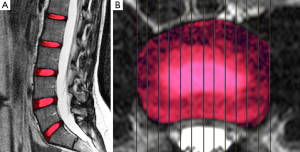

Five lumbar IVDs were manually segmented to the full extent, i.e., encompassing the complete NP and AF, considering all sagittal slices and taking care not to segment the subchondral bone and vertebral endplate, in the last echo image (TE =160 ms) of the T2 multiecho acquisition (Figure 2A).

Another segmentation was performed using only the central sagittal slice of each lumbar MRI using regions of interest (ROIs) of fixed dimensions (26.77 mm2) and positioned at the NP, anterior annulus fibrosus (AAF) and posterior annulus fibrosus (PAF) (Figure 2B). Our ROI positioning methodology was similar to the manual approach of Mok et al. (15). The nucleus ROI was placed in the most central area of the disc. The annulus ROI were positioned in the most anterior and posterior portions of the disc. A clear separation of NP and inner AF was not possible especially for degenerated discs. The endplates and ligaments would all appear as dark signals on T2-weighted images, therefore, sufficient space was allowed for dark signal band near the endplate, near the anterior border close to the abdominal fat, and near the posterior border close to the spinal fluid.

After the volumetric segmentation, the IVD volumes were obtained from the disc labels. These labels were superimposed in the relaxometry maps to extract T1ρ and T2 values (Figure 3).